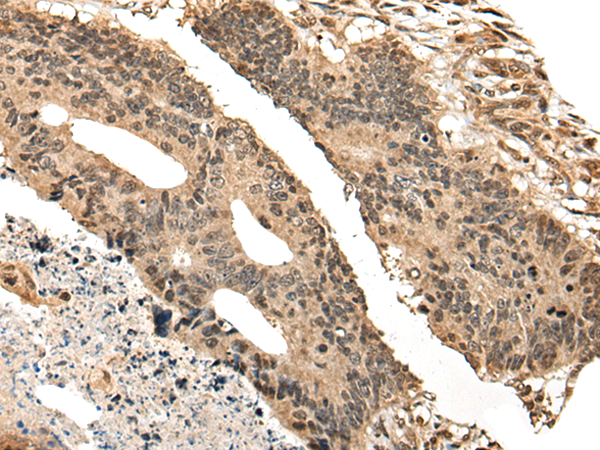

分类: 科研抗体货号: P09447别名: JM11应用: IHC反应种属: Human, Mouse